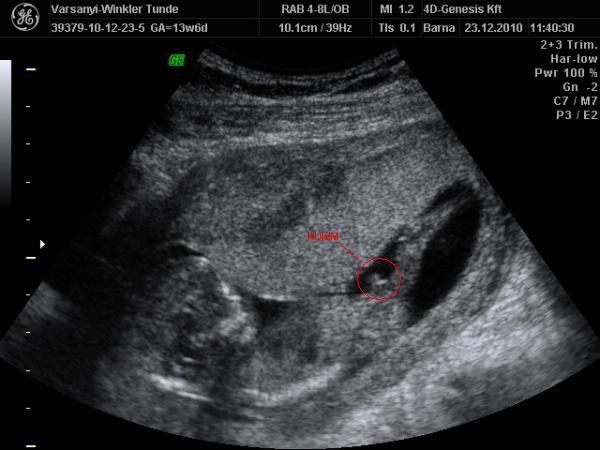

Bár tegnap a dokor bácsi azt mondta, hogy azért lassan vissza kellene vennem a lendületből, mert nem lesz jó vége. Manócska jól van, de tegnap nem tudtuk megnézni. Hasi uh-val próbálkozott, de pont úgy fordult, hogy csak a nagy kobakját láttuk

Gondolta, ha arra van a feje, akkor lentről lehet látni valamit a neméből.

Be is terpesztett rendesen, mint egy kis utcalány

Természetesen lánynak is látszott, bár azt mondta, hogy még ne éljük bele magunkat. A férjem le is tört egy kicsit, de nem vallotta volna be.Holnap reggel megyek AFP-re.